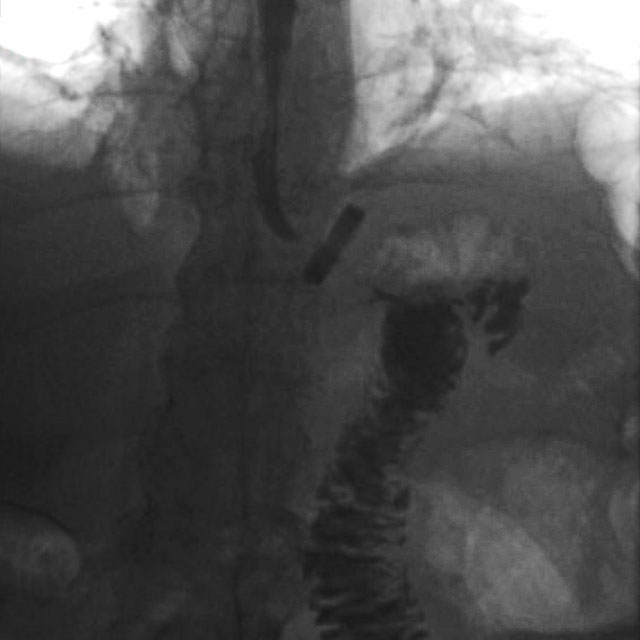

The ring is visible on X-ray due to the bariumsulphate with which the medical grade silicone is mixed (see fig. 2).

Fig. 2: X-ray of bypass with MiniMIZER RING (courtesy Dr. Focquet, Dr. Mathyssen)